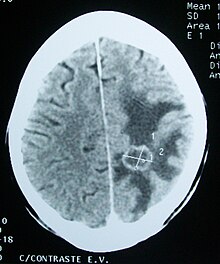

Medical imaging plays a central role in the diagnosis of brain tumors. Early imaging methods – invasive and sometimes dangerous – such as pneumoencephalography and cerebral angiography have been abandoned in favor of non-invasive, high-resolution techniques, especially magnetic resonance imaging (MRI) and computed tomography (CT) scans, though MRI is typically the reference standard used.[37] Neoplasms will often show as differently colored masses (also referred to as processes) in CT or MRI results.

This is because these tumors disrupt the normal functioning of the BBB and lead to an increase in its permeability. More recently, advancements have been made to increase the utility of MRI in providing physiological data that can help to inform diagnosis and prognosis. Perfusion Weighted Imaging (PWI) and Diffusion Weighted Imaging (DWI) are two MRI techniques that reviews have been shown to be useful in classifying tumors by grade, which was not previously viable using only structural imaging.[38] However, these techniques cannot alone diagnose high- versus low-grade gliomas, and thus the definitive diagnosis of brain tumor should only be confirmed by histological examination of tumor tissue samples obtained either by means of brain biopsy or open surgery. The histological examination is essential for determining the appropriate treatment and the correct prognosis. This examination, performed by a pathologist, typically has three stages: interoperative examination of fresh tissue, preliminary microscopic examination of prepared tissues, and follow-up examination of prepared tissues after immunohistochemical staining or genetic analysis.